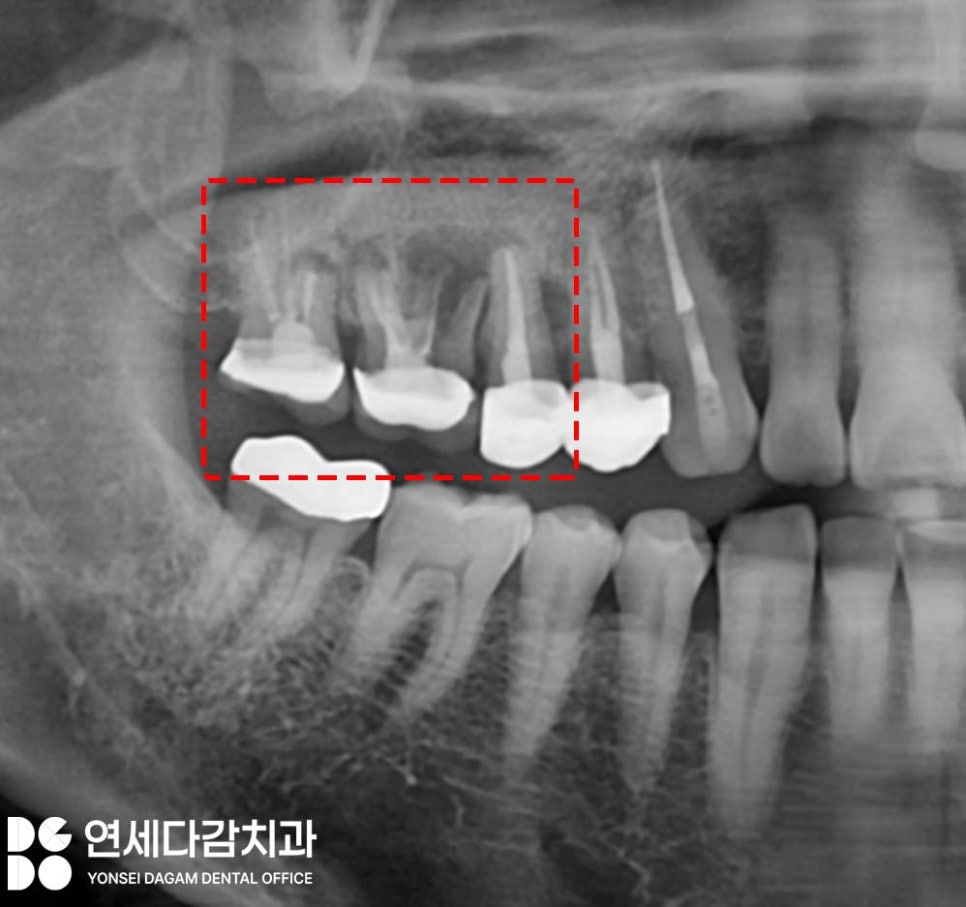

위 내용에 해당되는 케이스에서

사진에 표시한 부위를 살펴보면,

오른쪽 위 어금니 부위 치근 주변으로

심한 염증이 진행되고 있었습니다.

지지해 줄 뼈가 염증에 의해 소실되어

이가 흔들리고 있었으며

심한 악취와 고름이

배출되는 상태였습니다.

자세히 관찰해 보니

해당 어금니 중 하나는

뿌리 부위인 치근이

파절된 양상도 보였습니다.

더 이상 보존할 수 없는 상태로

발치 후 임플란트로 회복이

필요한 상황이었습니다.

그러나 해당 부위는 치근 부위와

상악동이 근접해 있는 위치이기 때문에